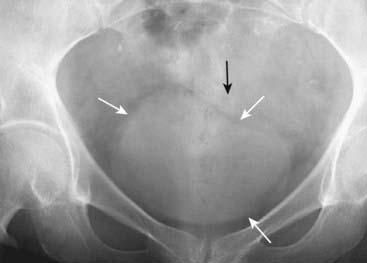

Figure 13-1 Normal supine abdomen.

This is the “scout” film of the abdomen, the one that gives a general idea of the bowel gas pattern and allows you to search for radiopaque calculi and detect organomegaly. There is usually a small amount of air in about two to three loops of nondilated small bowel (solid black arrow). There will almost always be air in the stomach (dotted black arrow) and in the rectosigmoid (solid white arrow). Depending on the amount of fat around the visceral organs, their outlines may be partially visible on conventional radiographs. The psoas muscles are outlined by fat (dotted white arrows) making them visible on this image.